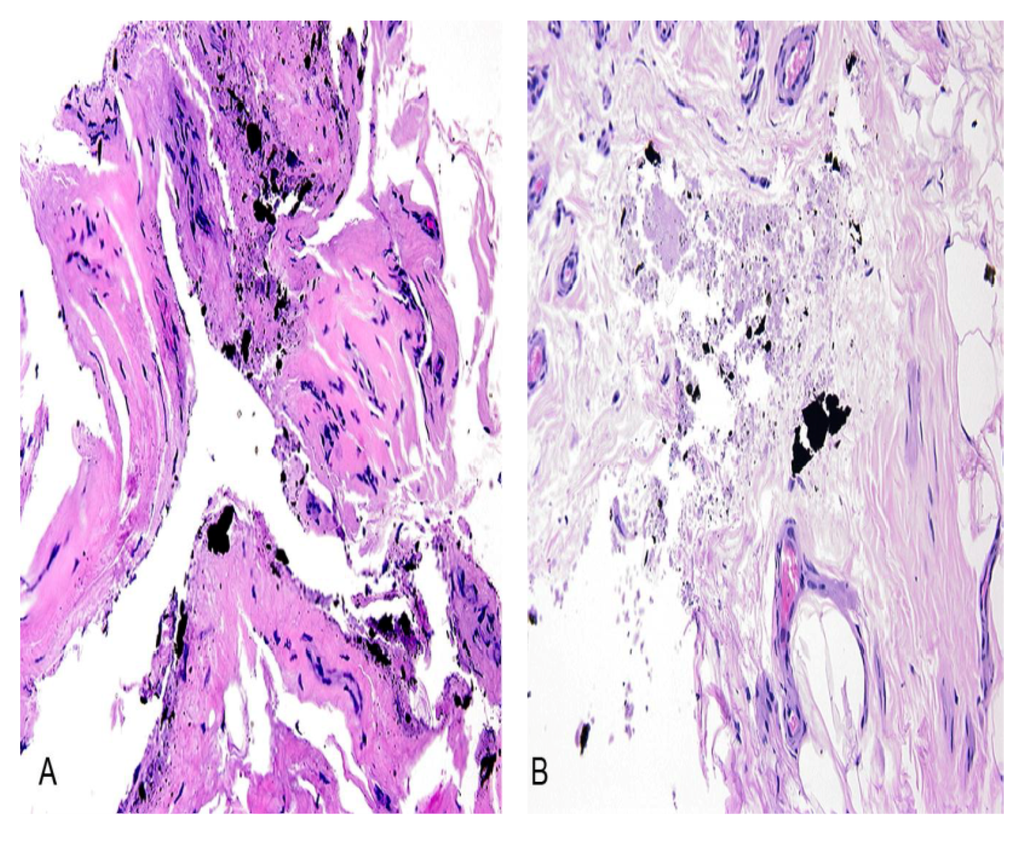

3.2.1. Case Number 1

3.2.3. Case Number 3

3.2.4. Case Number 4